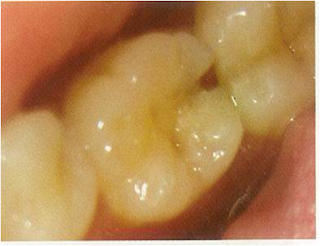

Pit and Fissure caries

- Highest prevalence of all caries bacteria rapidly colonize the pits and fissures of the newly erupted teeth

- These early colonizers form a “bacterial plug” that remains in the site for long time ,perhaps even the life of the tooth

- Type & nature of the organisms prevalent in the oral cavity determine the type of organisms colonizing the pit & fissure

- Numerous gram positive cocci, especially dominated by s.sanguis are found in the newly erupted teeth.

- The appearance of s.mutans in pits and fissures is usually followed by caries 6 to 24 months later (Window Period).

- Sealing of pits and fissures just after tooth eruption may be the most important event in their resistance to caries.

- Shape, morphological variation and depth of pit and fissures contributes to their high susceptibility to caries.

- Caries expand as it penetrates in to the enamel.